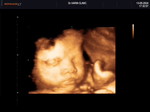

แม่ๆบ้านไหน เข้าเดือนที่ 7 ปวดเมื้อย รู้สึกว่าไม่ไหวบ้างคะ

กำลังตั้งครรภ์